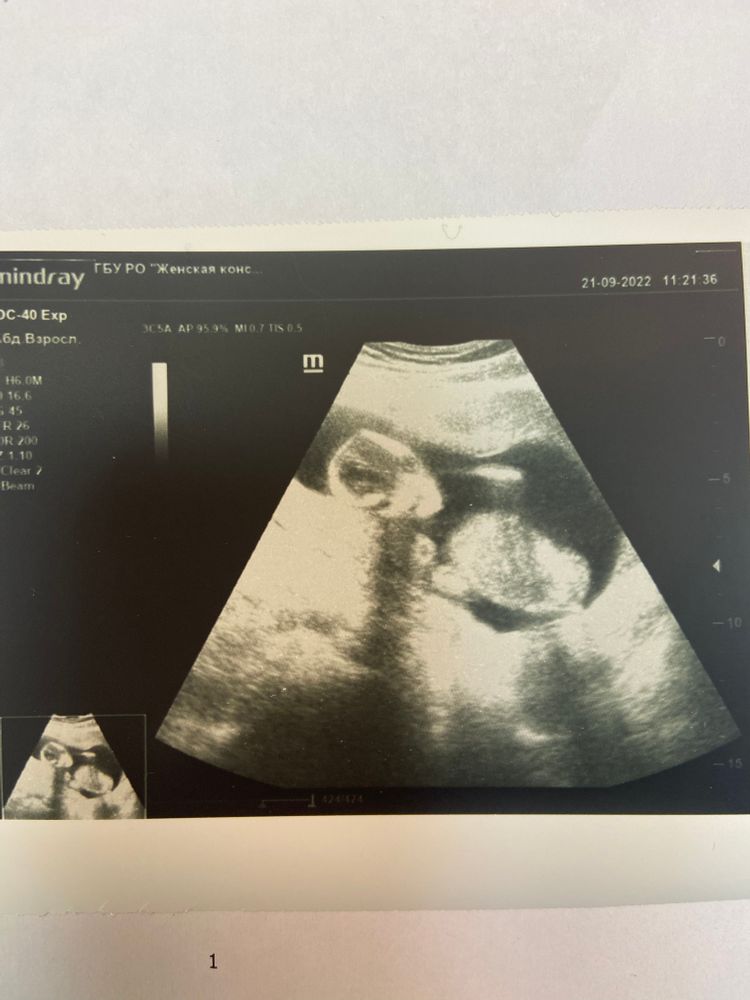

фото с Узи не очень удачное)похож на нло))) но вот так повернулся в этот раз 😁🙏🏼